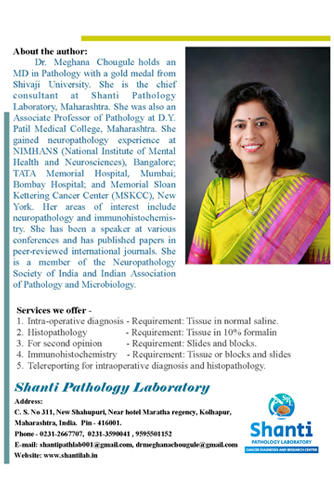

Dr. Meghana Chougule is the chief consultant pathologist at Shanti Pathology Laboratory Cancer Diagnosis & Research Center, Maharashtra.

She has completed MBBS from Government Medical College, Miraj. She stood first and bagged a gold medal in MD in

Pathology examination in Shivaji University. She was felicitated with "Manohar Kirloskar award"